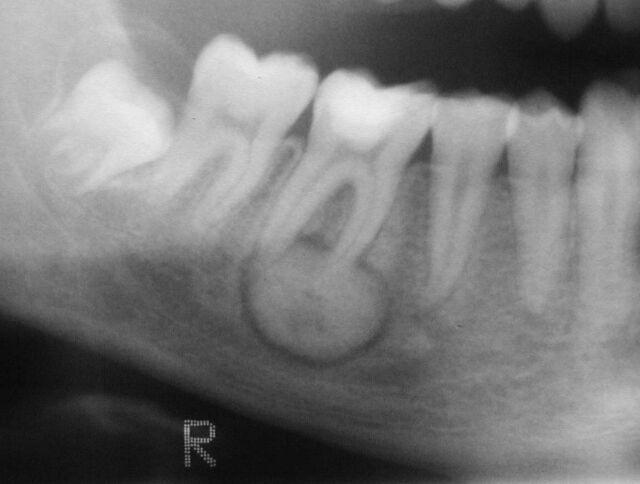

Massive osteolysis

Gorham Disease

spontaneous and progressive destruction of one or more bones - affected area does not regenerate or repair

Destroyed bone is initially replaced by vascular proliferation

Eventually filled with dense fibrous tissue

No known cause

Mandible affected more than maxilla

Treatment: Surgical and bisphosphonates

Surgical + bone graft –> bone graft will undergo osteolysis (not a successful treatment)

Massive osteolysis signs and symptoms

Mobile teeth

Pain

Malocclusion - movement of teeth

Deviation of the mandible

Clinically obvious deformity

Pathologic fracture

Massive osteolysis xray manifestation

Radiolucent foci of varying size with indistinct margins

Coalesce to become larger - involve cortical bone

Large prortions of invovled bone disappear

Loss of lamina dura